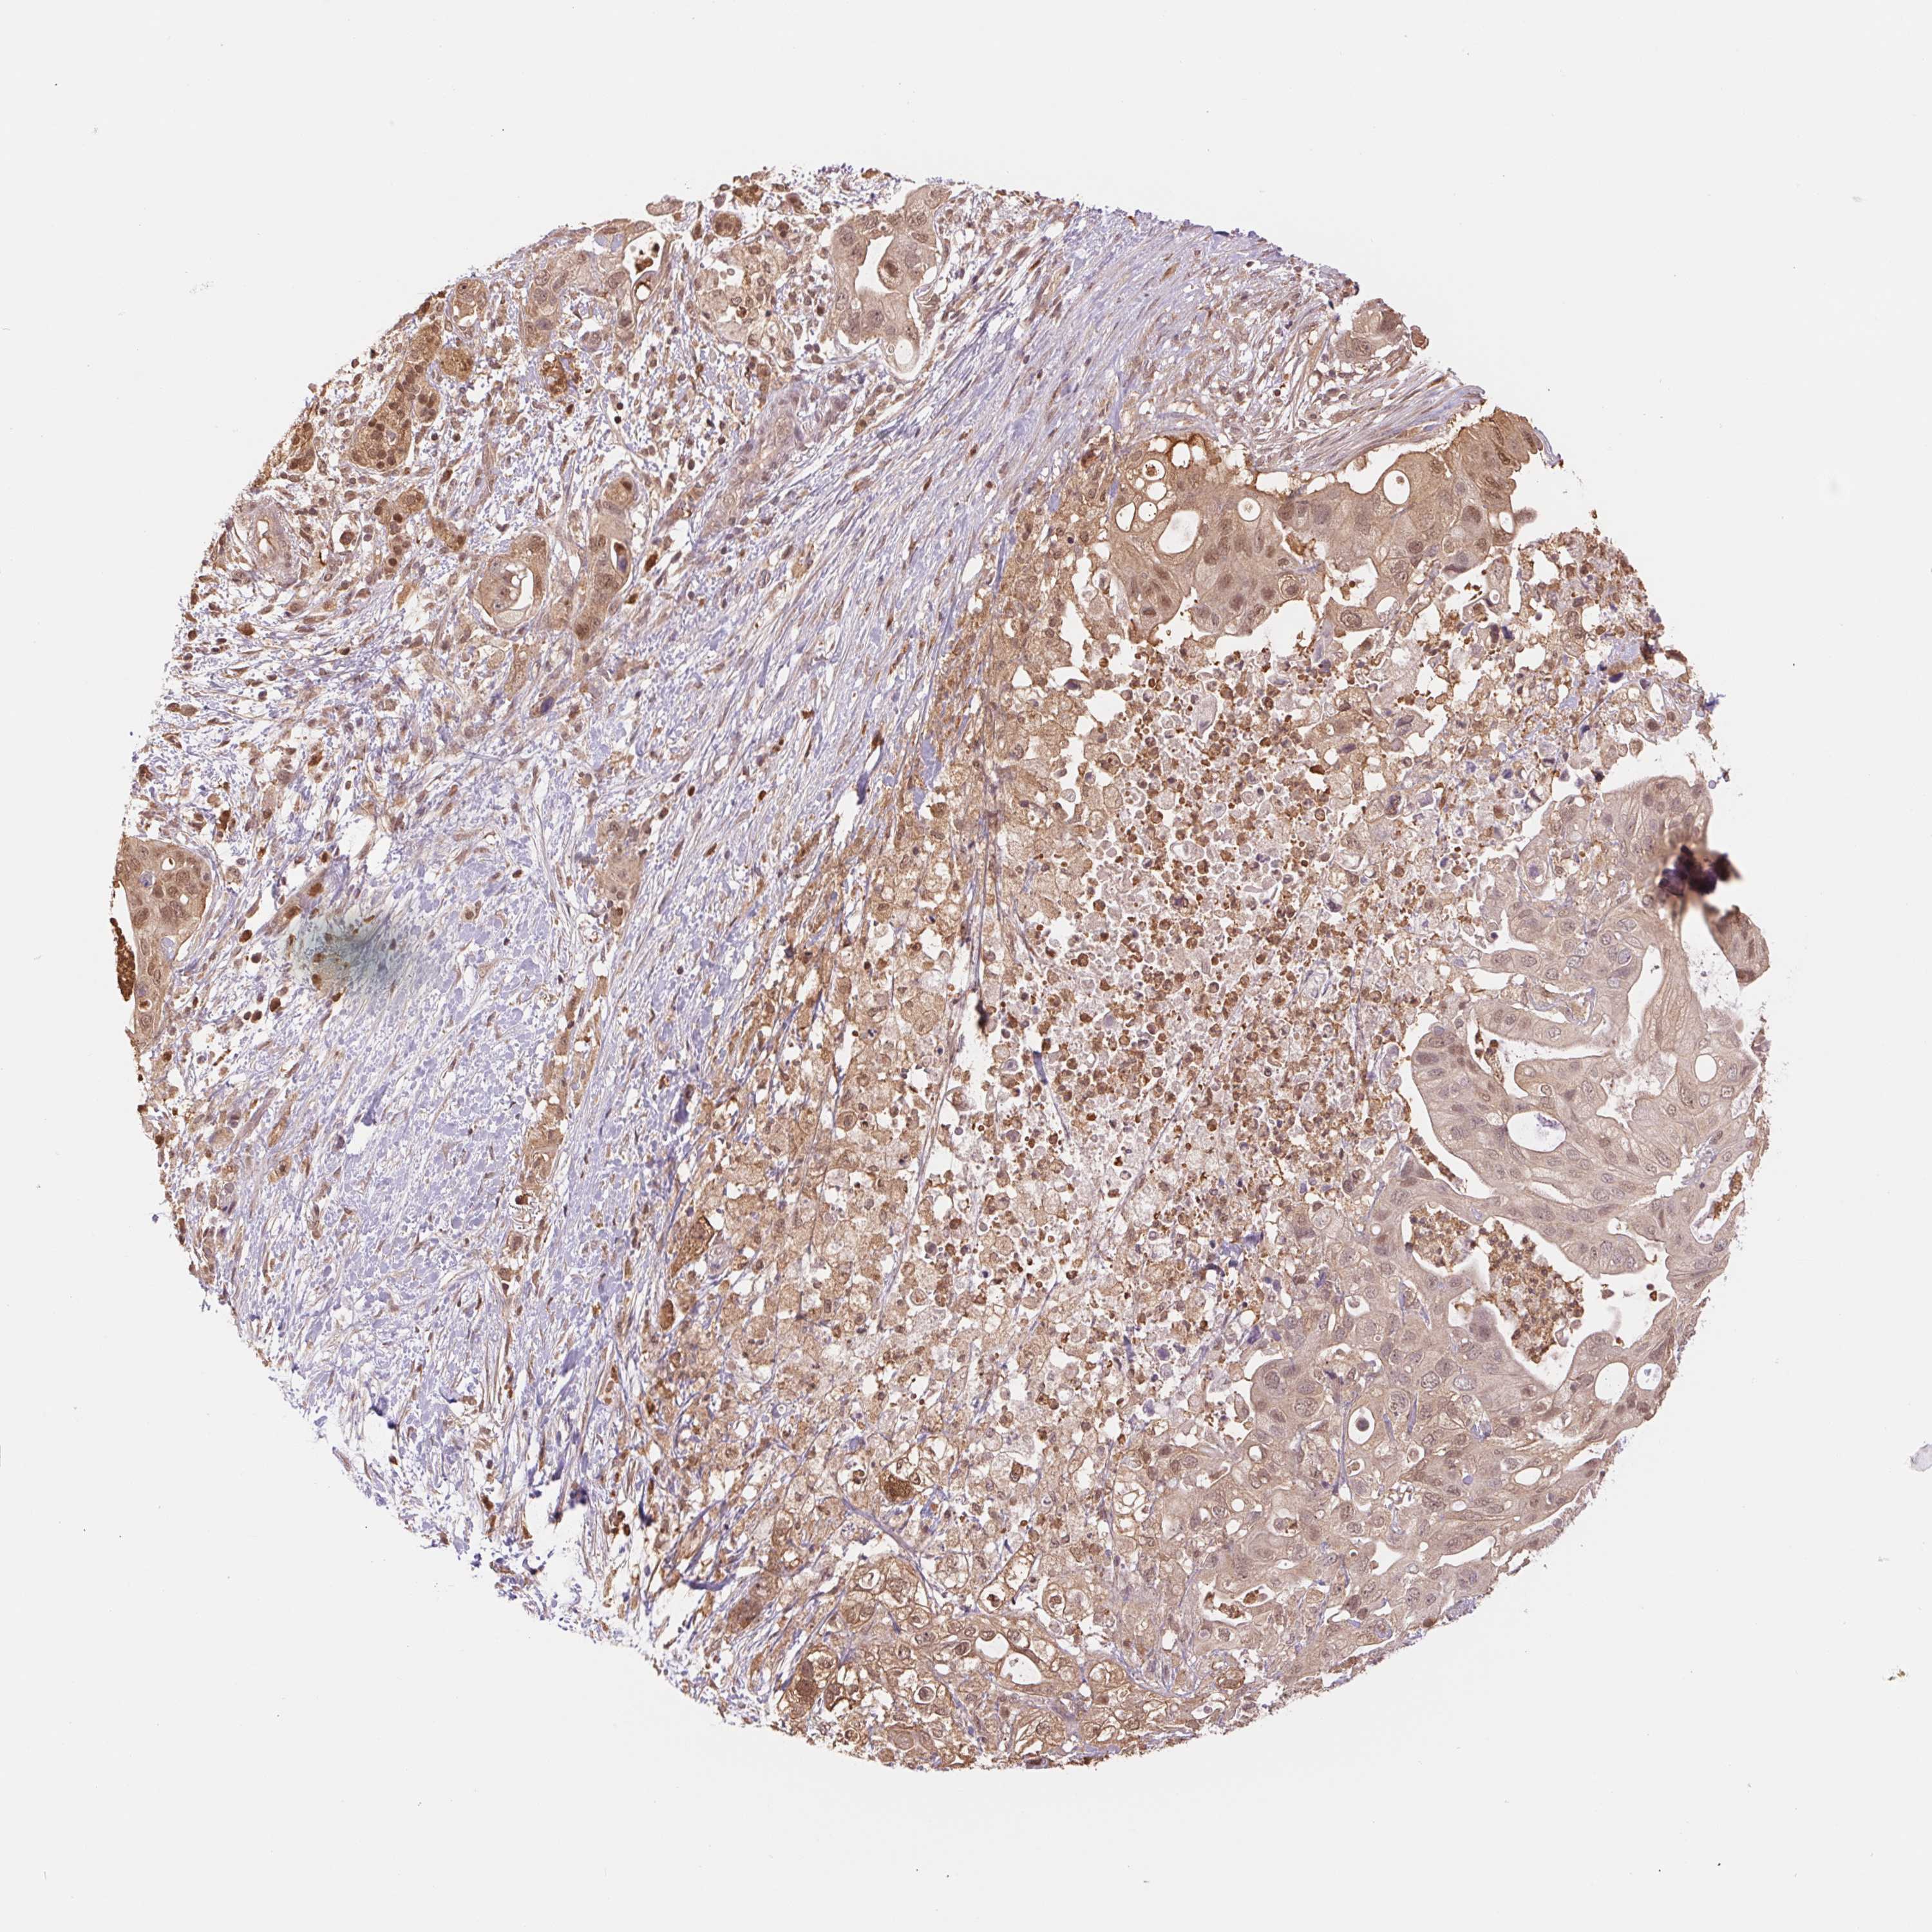

PANCREATIC CANCER - Protein expressioni

A mouse-over function shows sample information and annotation data. Click on an image to view it in a full screen mode. Samples can be filtered based on level of antibody staining by selecting one or several of the following categories: high, medium, low and not detected. The assay and annotation is described here.

Note that samples used for immunohistochemistry by the Human Protein Atlas do not correspond to samples in the TCGA dataset.

Antibody stainingi

Antibody staining in the annotated cell types in the current human tissue is reported as not detected, low, medium, or high, based on conventional immunohistochemistry profiling in selected tissues. This score is based on the combination of the staining intensity and fraction of stained cells.

Each image is clickable and will lead to virtual microscopy that enables deeper exploration of all samples and also displays staining intensity scores, fraction scores and subcellular localization as well as patient and tissue information for each sample.

Antibody HPA037830

Antibody HPA057540